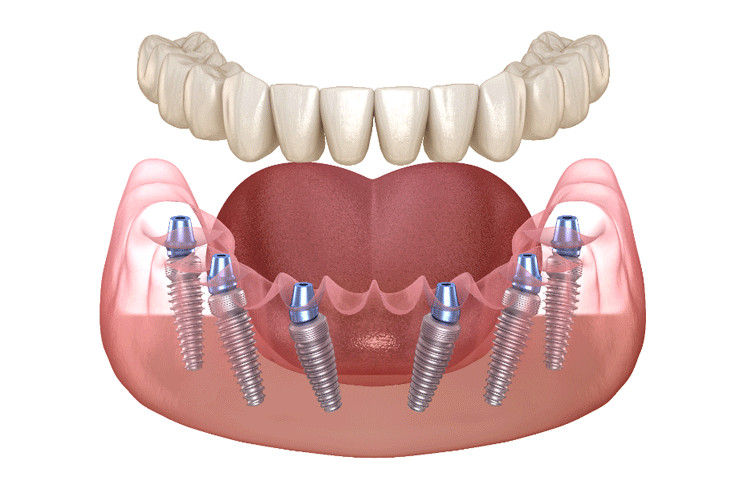

インプラント

長年の研究と高度な技術のもとに開発された人工の歯根(インプラント)を植える治療法

![]() |